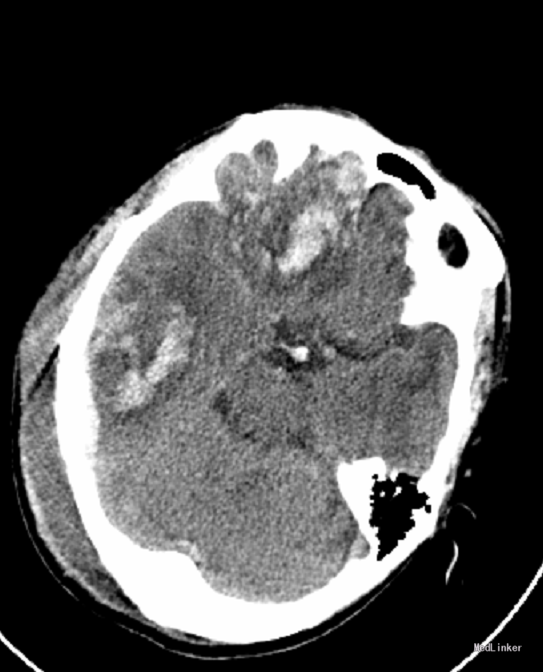

神志昏迷,GCS6分,双侧瞳孔等大3mm,对光反应灵敏,口角不歪,颈软,四肢肌力检查不配合,肌张力可,病理反射未引出。本院头颅CT检查提示:右侧额颞枕多发脑挫裂伤伴血肿、右枕骨骨折、蛛网膜下腔出血、右枕头皮血肿。

初步诊断:极重型颅脑外伤:右侧额颞枕多发脑挫裂伤伴血肿、蛛网膜下腔出血、右枕骨骨折、右枕头皮血肿. 急诊行开颅血肿清除术+去骨瓣减压术+颅内压探头置入术。

术后复查头颅CT提示:两侧额叶、颞叶脑挫裂伤术后改变。右侧顶叶挫裂伤。右颞枕部硬膜外/下血肿较前片2015.06.08缩小。蛛网膜下腔出血;右颞骨岩部骨折;右枕部头皮血肿。松果体区条状钙化密度影,必要时MRI检查。术后给予安可欣预防感染,德巴金预防癫痫,营养神经及补液等治疗。